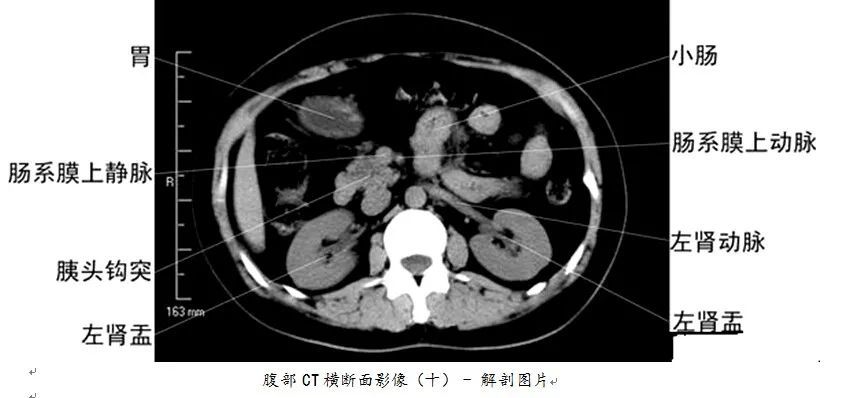

详细的全身ct图谱,赶紧收藏了吧!

【医科普】全身ct图谱,速收藏!

全身ct高清图谱建议收藏